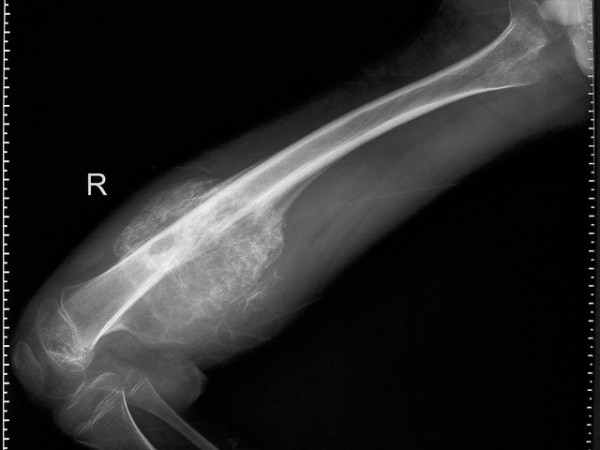

In Fase attiva nell'Osso avviene una Osteolisi, una rarefazione ossea fino alla creazione di veri e propri geodi. In questa fase il rischio di fratture spontanee è limitato in quanto il Periostio ancora ha una discreta tenuta.

Nella Fase di riparazione il tessuto osseo viene rigenerato con la comparsa di una leucemia o dell'osteosarcoma. Questo per rinforzare la struttura dell'osso e della personalità. In questo momento il Dolore è molto forte e il rischio di fratture spontanee è elevato in quanto il periostio si è ammorbidito.